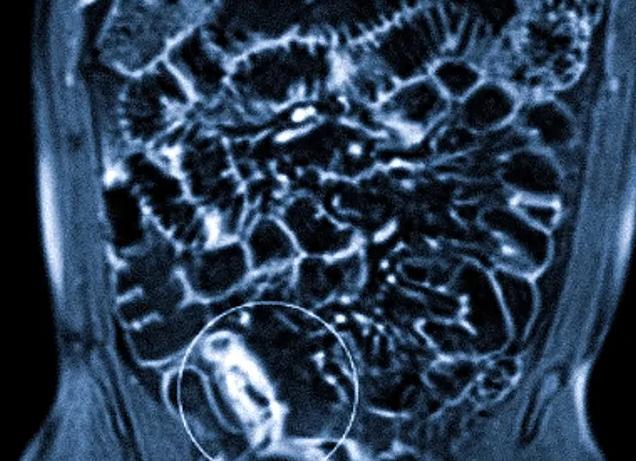

ЖКТ (желудочно-кишечный тракт) отличается особым строением. Диагностика данной системы недоступна для общего визуального осмотра, поэтому следует задействовать специальные компьютерные технологии. Следует отметить, что диагностика тонкой кишки (либо других отделов кишечника) используется редко, но является наиболее эффективным. Магнитные поля сканируют тонкие кишки, ткани внутренних органов делают их фотографию в формате 3D.

Больной помещается на аппаратный стол в положении лёжа. Для предотвращения непроизвольных движений пациента во время проведения исследования, руки и ноги подлежат фиксации. Стол перемещается внутрь кольца, которое продуцирует магнитное излучение так, чтобы само поле находилось в проекции исследуемого органа, в нашем случае – тонкого кишечника. После этого магнитное кольцо приводится в движение по кругу, производя магнитное напряжение и получая ответный сигнал от органов и систем организма, которые находятся в поле воздействия. Полученный результат обследования в виде 3D-изображения передаётся на компьютерный монитор и записывается.

Так как тонкий кишечник является полым органом, его осмотр в ряде случаев оказывается затруднён, а наличие новообразований, болезни Крона или дивертикулов визуально может выглядеть как имитация складок стенки кишки. Для наполнения просвета кишечника и растяжения его стенок производится гидро-МРТ. Для этого перед исследованием пациенту необходимо выпить 1-1,5 литра раствора сорбитола (или маннитола).

По данным обследования можно выявить наличие новообразований тонкого кишечника, двенадцатиперстной кишки, утолщение стенок, признаки кровотечения, увеличение лимфоузлов корня брыжейки и наличие в них метастазов или прорастания опухоли, дивертикулы, сужение просвета, стриктуры, стенозы, болезнь Крона и другие морфологические изменения структуры.

Гидро-МРТ позволяет достоверно установить дивертикулы и болезнь Крона, которые другими диагностическими методами выявить довольно сложно.